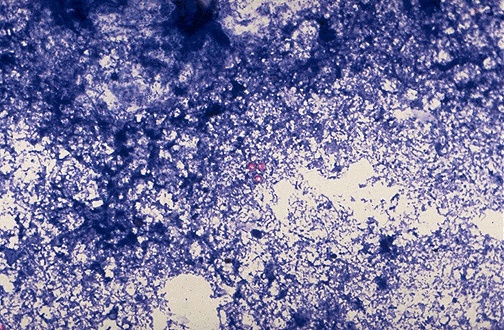

Cryptosporidiosis from infection by Cryptosporidium parvum protozoa is diagnosed in this stool specimen with acid fast stain that highlights these small red-staining organisms.